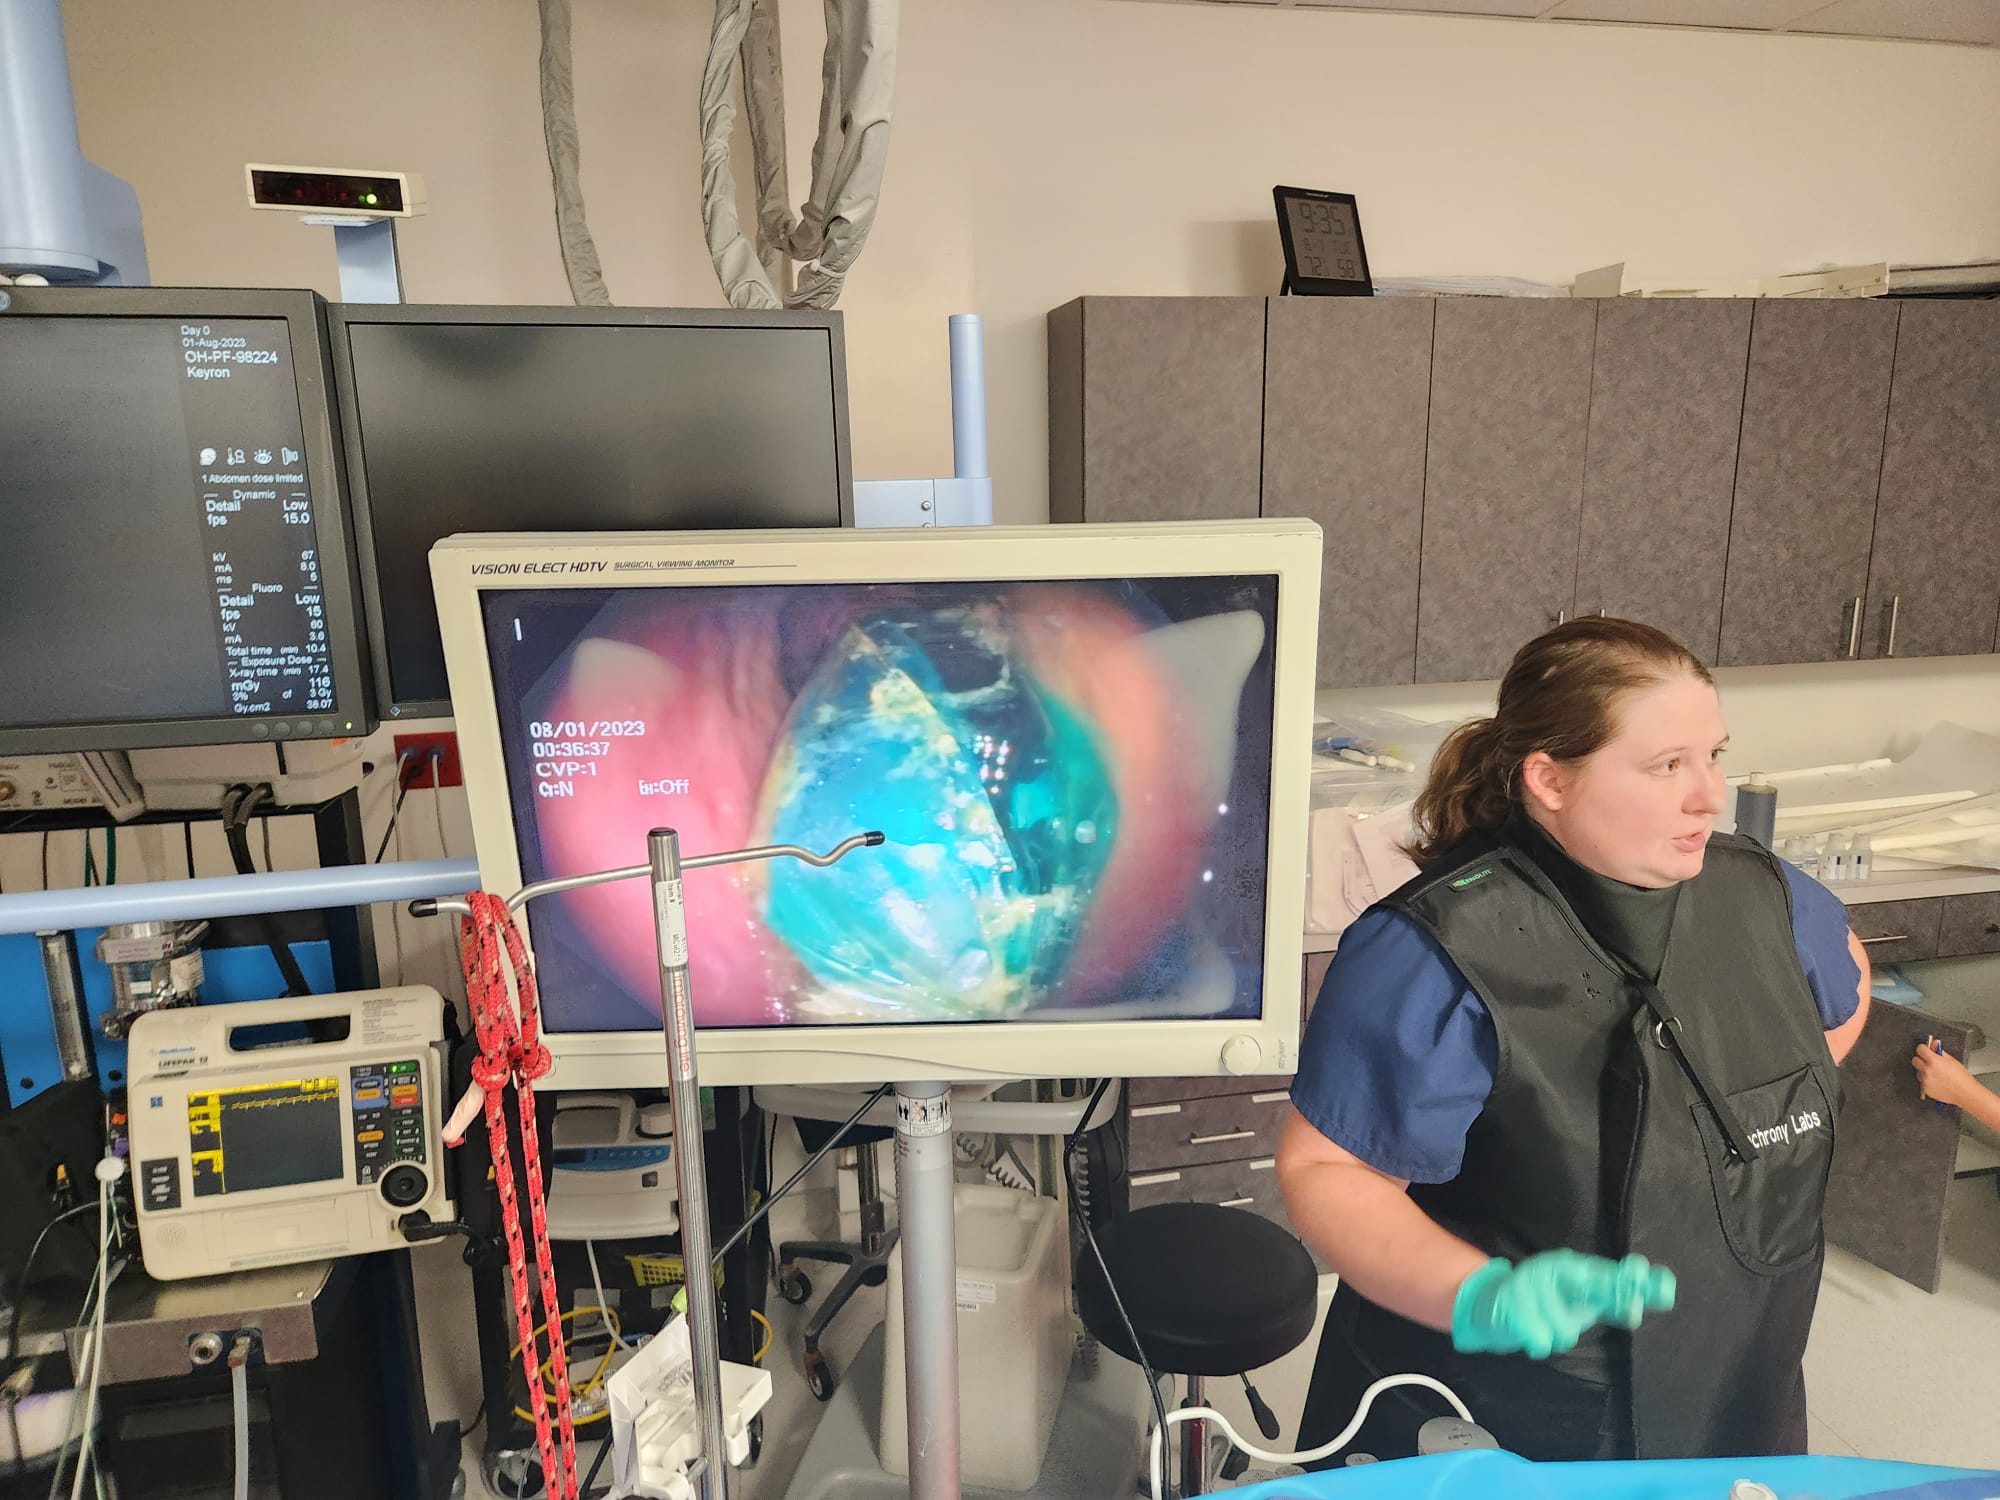

Long-Term Safety & Efficacy in Swine

Proven Long-Term Safety

Proven Correct and Stable Long-Term Positioning